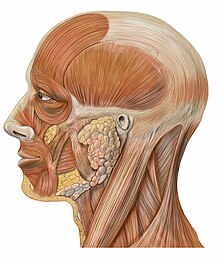

Muscles et vaisseaux de la face

Muscles et innervation faciales Muscles et glandes salivaires

Muscles et glandes salivaires